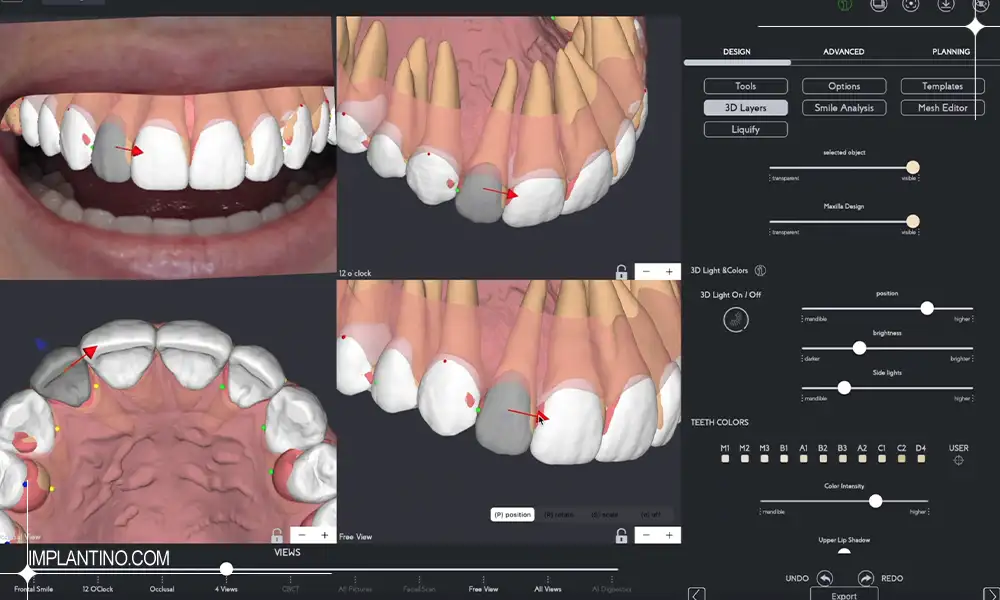

فرآیند طراحی لبخند دیجیتال با گرفتن عکس ها و اسکن های سه بعدی دقیق از دندان ها و صورت بیمار آغاز می شود. سپس این تصاویر وارد نرم افزارهای تخصصی می شود تا طرح های مختلف لبخند با توجه به ساختار صورت، لب ها و ویژگی های فردی طراحی شوند. بیمار می تواند این طرح ها را به صورت مجازی مشاهده کند و نظرات خود را بیان کند. پس از تایید نهایی، دندانپزشک بر اساس این طرح، درمان های زیبایی مانند لمینت، کامپوزیت یا ارتودنسی را اجرا می کند. این روش باعث کاهش خطا و افزایش هماهنگی بین خواسته بیمار و نتیجه درمان می شود.

- اسکن سه بعدی دیجیتال: استفاده از دستگاه های اسکن داخل دهانی برای دریافت تصاویر دقیق از دندان ها و ساختار فک

- عکسبرداری دیجیتال حرفه ای: تهیه عکس های با کیفیت بالا از صورت و لبخند بیمار برای تحلیل دقیق تر

- نرم افزارهای طراحی لبخند: به کمک نرم افزارهای پیشرفته، طراحی و شبیه سازی لبخند ایده آل بر اساس ویژگی های صورت انجام می شود

- تولید نمونه های آزمایشی (موکاپ): ساخت نمونه های موقتی از طرح لبخند برای آزمایش و مشاهده در دهان بیمار قبل از اجرای نهایی

- پرینت سه بعدی: در برخی موارد، مدل های فیزیکی لبخند طراحی شده با استفاده از پرینترهای سه بعدی ساخته می شوند تا دندانپزشک و بیمار بهتر تصمیم بگیرند